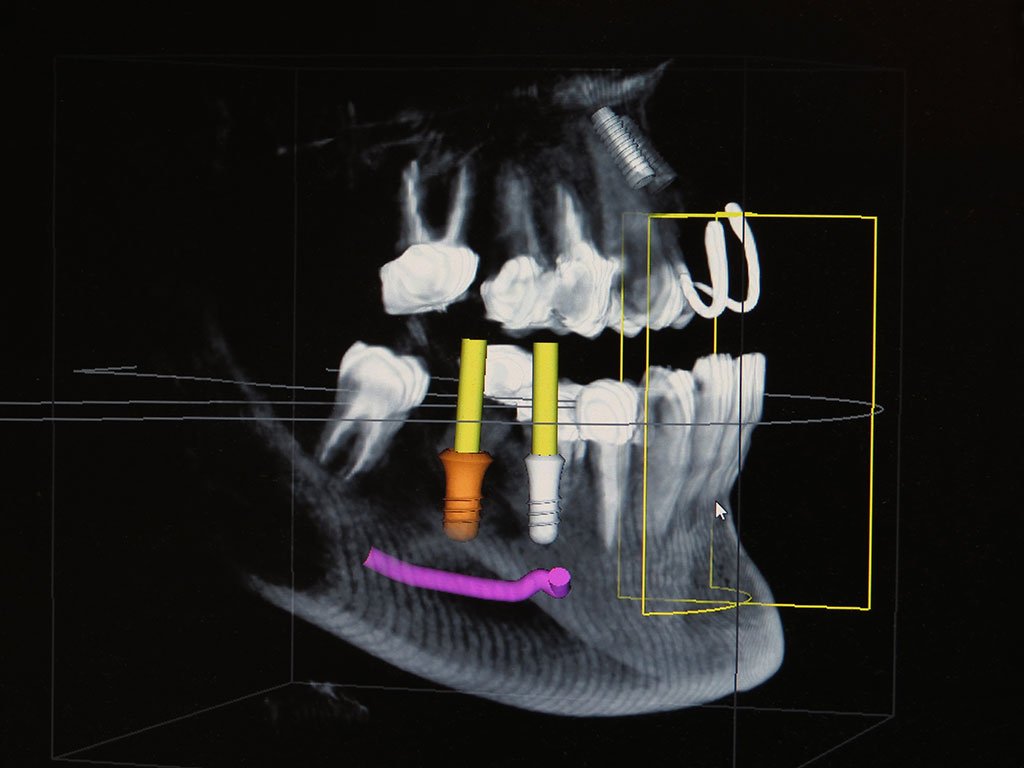

Our dentists are able to see a patient’s teeth and oral structures with more detail and accuracy than ever before. Beyond the accuracy, unique view, and high resolution of images provided by our imaging system, another benefit to patients is that this system requires only a very low exposure to radiation.

Digital imaging is an amazingly helpful tool for various dental procedures such as dental implant restorations, gum analysis and treatment, orthodontic evaluations and endodontic concerns. Because nothing is left hidden from the dentist when this imaging system is used, your treatment can be more complete, with fewer surprises for your dental practitioners.